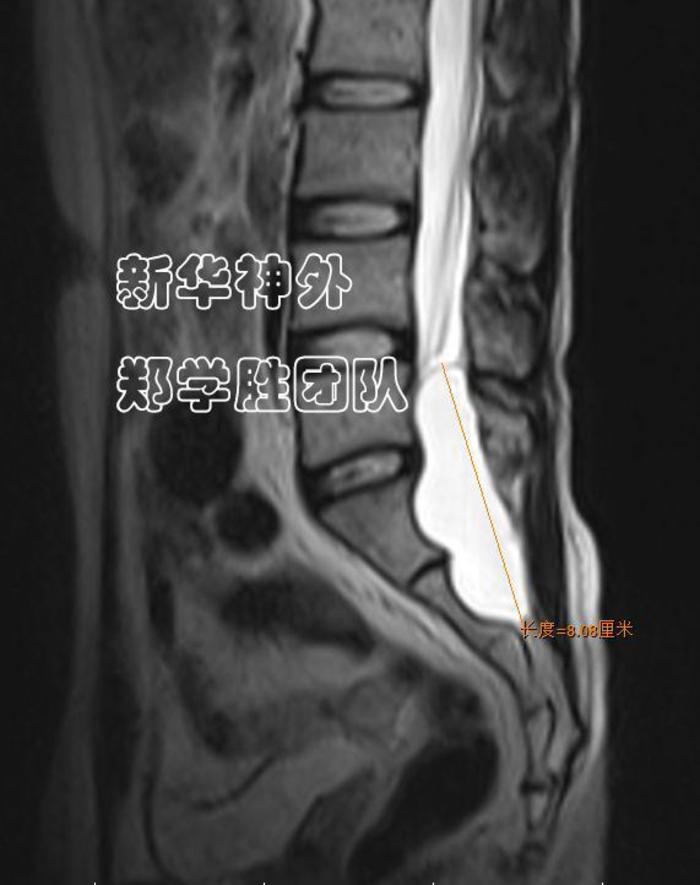

术前MRI显示:8cm巨大腰骶管囊肿;

水往低处流,难道漏口在腰5上段吗?

经过仔细读片,郑学胜主任判断,骶管囊肿漏口很可能在腰5骶1间隙(箭头所指),而不是在腰5上段。